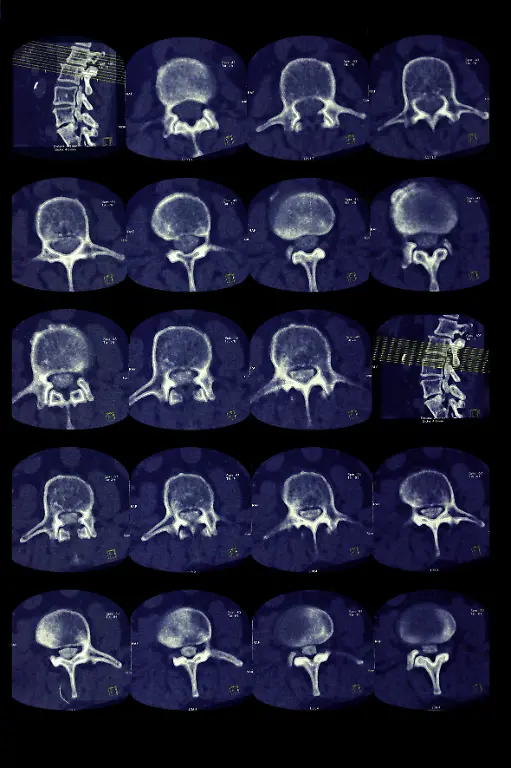

Er war ein Revolutionär der Medizintechnik: Der Physiker Wilhelm Conrad Röntgen entdeckte 1895 zufällig die X-Strahlen, was nicht nur für die Diagnostik in der Medizin ein Meilenstein war. Später wurden die Strahlen und das Verfahren nach ihm benannt. Röntgen starb vor 100 Jahren in München.